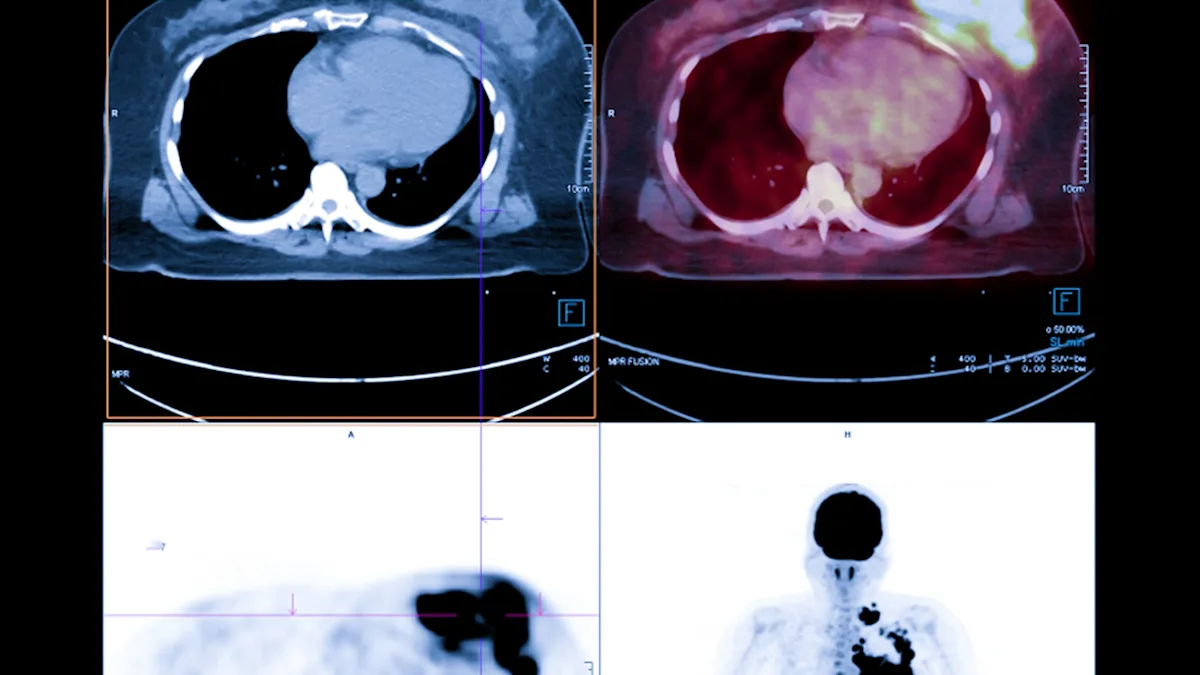

Eighth grader Anushka Sable has made a significant discovery during a school science project, finding that microplastics present in human immune cells can lead to the formation of tumor-like structures. Her research, conducted with a mentor at Emory University, involved exposing human monocytes to microplastics and observing their uptake of these particles. Further investigation using a 3D cell culture revealed the development of tumor-like formations, suggesting a potential link between microplastic presence in the body and cancer risk. This finding is particularly concerning given that microplastics have been detected in various human organs, including breast milk, placentas, and kidneys. Sable's work highlights the need for further study into the health implications of microplastic exposure and potential mitigation strategies.